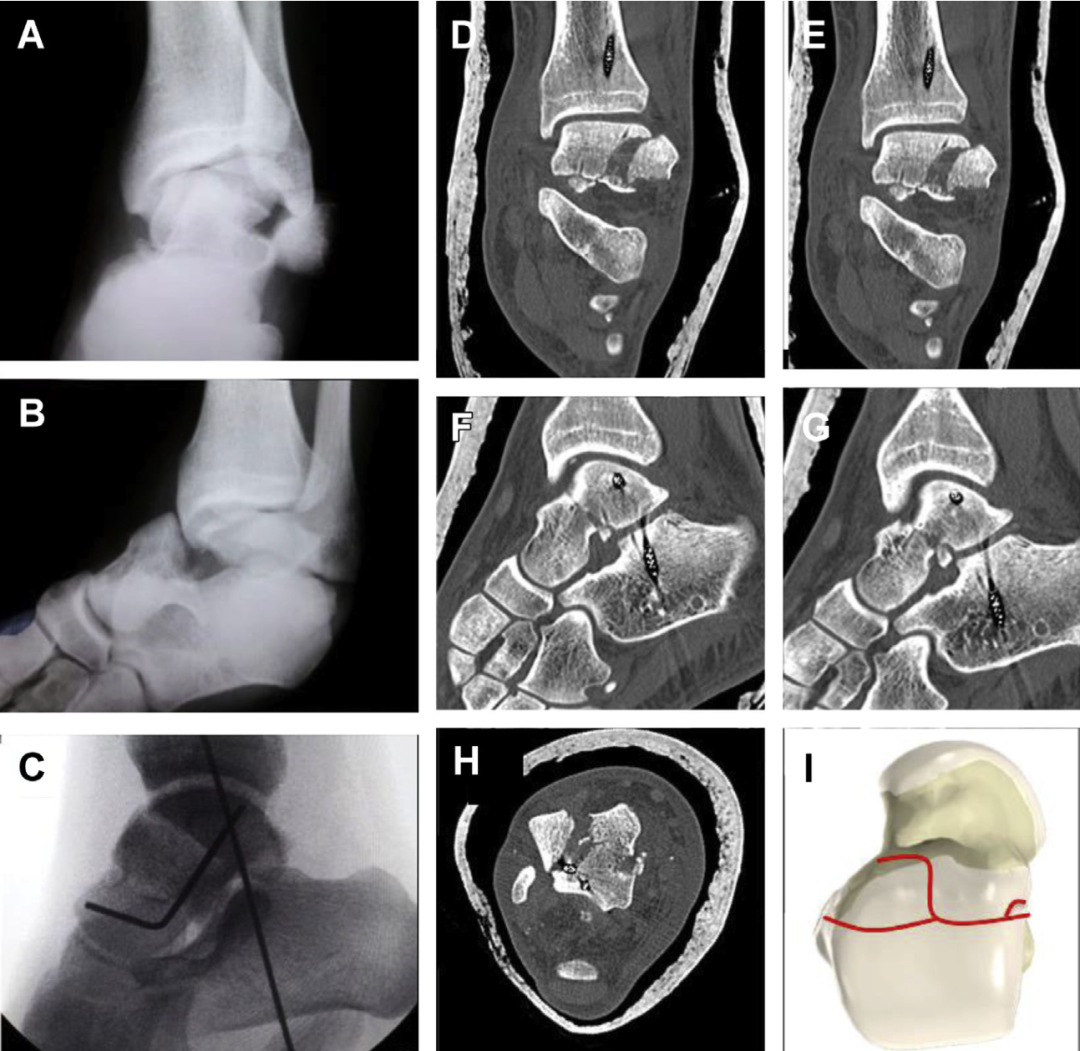

有 頭骨有 骨折有 桡骨远端骨折的治疗策略和入路选择-有 好医术文章-有 好医术-赋能医生守护生命有 桡骨远端骨折的治疗策略和入路选择-有 好医术文章-有 好医术-赋能医生守护生命有 男家中跌倒竟釀「手肘恐怖三聯症」!醫示警8大併發症:恐神經受損|Uho優活健康網有 距骨颈骨折:选单入路还是双入路?(附详细手术步骤)有 -有 上海开为医药科技有限公司--创伤、肢体矫形技术解决方案的专业服务商有 距骨颈骨折:选单入路还是双入路?(附详细手术步骤)有 -有 上海开为医药科技有限公司--创伤、肢体矫形技术解决方案的专业服务商有 有 有